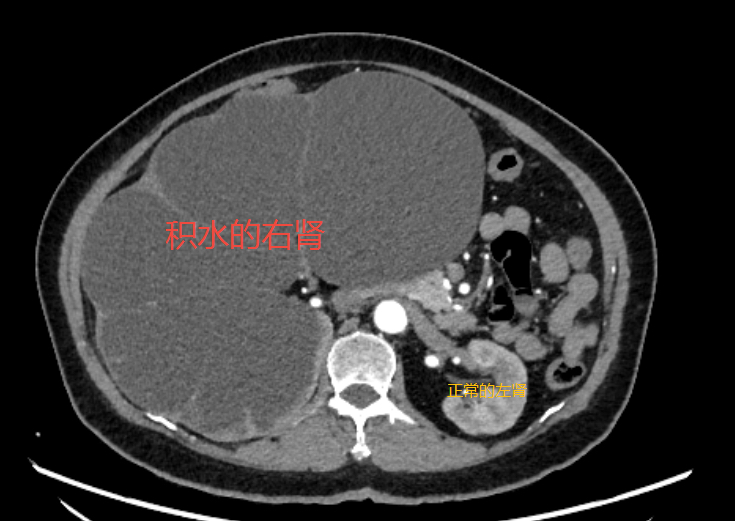

春节回家,长年在深圳打拼的小李(化名)看到自己60岁的老母亲比以往胖了不少,尤其是肚子,胖了两圈还不止,说是“怀胎十月”都不为过,可老人家说并没有感到不舒服,偶尔有点腰酸腰胀,忍一忍也就过去了。小李听后不放心,过完春节便马上带母亲来到大医院检查,结果发现老母亲的肚子居然是被右肾给填满了,此时的右肾已经像气球一样被吹到了将近40cm,并且里面充满尿液,功能也已丧失,而罪魁祸首竟是一颗“潜伏”在输尿管内的仅有0.8cm的结石。这颗从未引发疼痛的结石,像一道闸门,让她的肾脏在不知不觉中被积水“淹没”。

小李母亲的影像结果显示,她的右肾皮质已薄如纸片,且无血流信号——这正是肾脏“死亡”的表现。